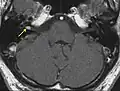

L'âge moyen d'apparition de la maladie est comprise entre 18 et 24 ans. Presque toutes les personnes atteintes développeront un schwannome vestibulaire devenant bilatéral avant l'âge de 30 ans. Les autres nerfs périphériques peuvent être atteints de schwannome ou de méningiome et rarement d'astrocytome ou épendymome. Une atteinte unique d'un nerf dans l'enfance responsable d'une paralysie faciale, d'un strabisme ou d'un pied et/ou d'une main ballante est un signe clinique de plus en plus fréquent vu dans l'enfance.

Le schwannome vestibulaire a pour conséquence une baisse de l'acuité auditive, qui est le premier symptôme, mais qui est retardé par rapport à l'apparition de la tumeur[7]. Elle peut être peu ressentie par le malade si l'atteinte est unilatérale, et devient très vite gênante si elle est bilatérale. L'évolutivité est cependant variable selon les individus et la taille de la tumeur n'est pas toujours correlée à l'importance de la gêne[8]. Le schwannome peut atteindre également d'autres nerfs crâniens, ainsi que la moëlle épinière.

Ce qui caractérise essentiellement la NF-2, c'est le développement de neurinomes bilatéraux (schwannomes) de la VIIIe paire de nerfs crâniens (retrouvés dans plus de 90 % des cas).

Révélés vers l'âge de 20-30 ans, ils constituent le problème majeur de la NF-2 par le retentissement sur l'ouïe, l'équilibre et aussi si leur développement comprime d'autres structures cérébrales.